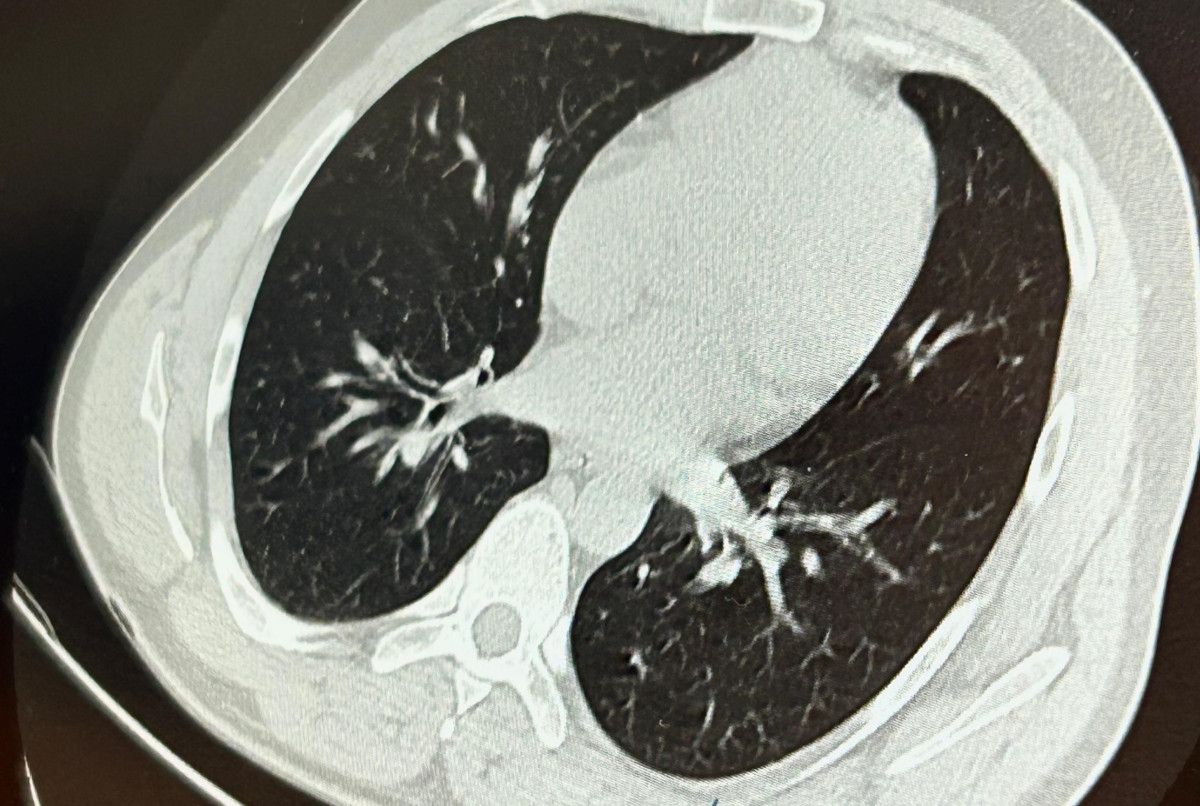

İlk olarak hastanenin ek hizmet binasında çekilen tomografi sonucunda, vidanın sol akciğerin hava yollarının yaklaşık dördüncü koluna kadar ilerlediği tespit edildiğini söz eden Op. Dr. Aksoy, şunları kaydetti:

Aynı gün hastamızı hazırladık. Bronkoskopi sırasında, implant vidasının sol üst lobun anterior segment bronşuna saplanmış konumda olduğunu gördük. Üroloji kısmında taş çıkarma süreçlerinde kullanılan aygıtla müdahale ettik.

Bunun üzerine toraks ve batın BT (bilgisayarlı tomografi) görüntülemesi istedik. Sonuçlarda implantın akciğerden çıktığı ve bedende rastgele bir yerde bulunmadığı tespit edildi” diye konuştu.